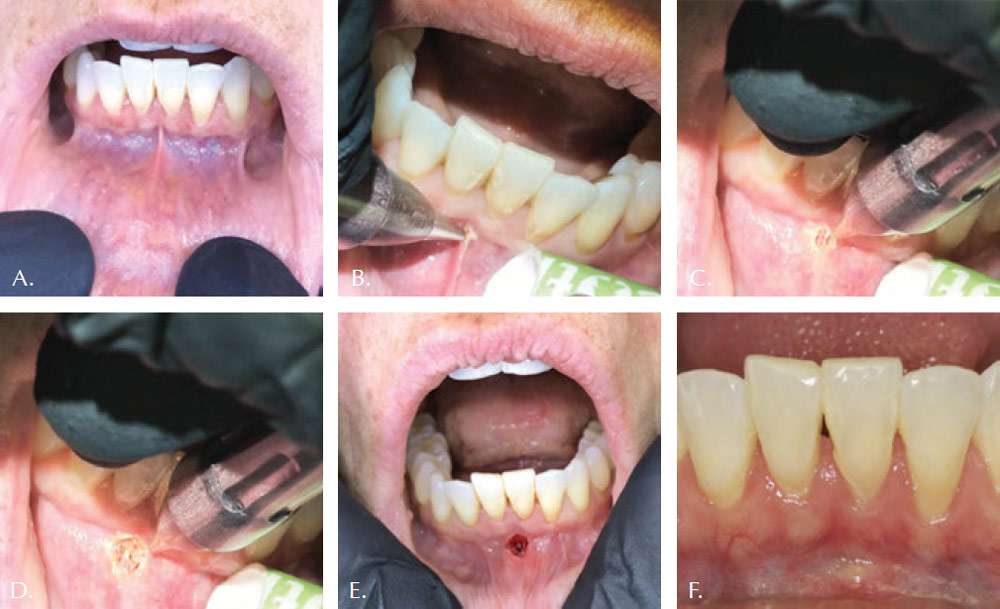

The osteopathically guided Functional Frenectomy (for both labial and lingual restrictions) is illustrated by the clinical case shown in Figures 1-3. Note both the immediately improved mobility and lift of the tongue. The well controlled hemorrhage, sealed lymphatics and reduced zone of thermal impact result in less edema and discomfort to the patient. Magnification during the frenectomy is strongly encouraged due to the close proximity of large blood vessels to the surgical site. The authors prefer using topical anesthesia to increase the reliability of the functional assessment during the release. However, the patient in this case felt the laser at times and small amounts of local anesthetic were administered to the upper and lower frenectomy sites.

In order to achieve the proper myofascial release in adult patients, it is not sufficient to just remove the aberrant frena. Under the osteopathic guidance, the clinician should often re-access the effect of the restriction release on other myofascial structures. The clinician must take into account the jaw range of motion, the floor of the mouth flexibility, along with the tongue’s ability to elevate, protrude, and achieve lateral functions. The clinician should proceed slowly and cautiously. It is important to remember that full range of motion is not always possible due to other limitations, i.e., clinician needs to know when to stop to achieve the maximum benefit. Frenum that restricts proper lingual or labial motion feels tight to finger pressing in. Unrestricted tongue and lips feel soft. To feel for restrictions, one can grasp the tip of tongue or lip with gauze and gently pull the tongue upwards and the lip outwards. Finger pressure of the other hand could help reveal accessory restrictions as push back would be felt. In this case study, the clinician used the tongue director as a probe to apply pressure to the points that appeared restrictive, and removed those fibers, or not, depending on the real-time osteopathic feedback from Dr. Geis.